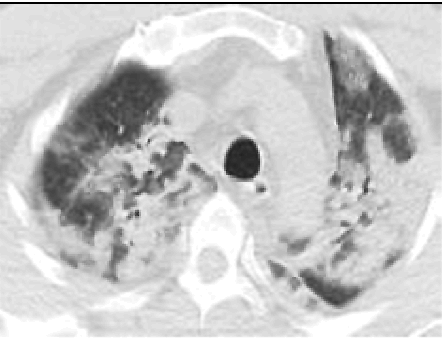

2. Наличие клинических проявлений, указанных в подпункте 1 пункта 1.3 настоящих Методических рекомендаций, в сочетании с характерными изменениями в лёгких по данным компьютерной томографии грудной клетки (далее - КТ ОГК) (приложение 1 к настоящим Методическим рекомендациям) вне зависимости от результатов однократного лабораторного исследования на наличие РНК SARS-CoV-2 и эпидемиологического анамнеза.

- Изменения в лёгких при КТ, типичные для вирусного поражения (объём поражения минимальный или средний; КТ 1-2),

- Изменения в лёгких при КТ, типичные для вирусного поражения (объём поражения значительный или субтотальный; КТ 3-4),

- Изменения в лёгких при КТ, типичные для вирусного поражения (объём поражения значительный или субтотальный; КТ 3-4),

- ОДН с необходимостью респираторной поддержки (инвазивная вентиляции лёгких, ЭКМО), Изменения в лёгких при КТ типичные для вирусного поражения критической степени (объём поражения значительный или субтотальный; КТ 4) или картина ОРДС - Снижение уровня сознания. |

С практической точки зрения наиболее важно пациентам с подозрением на коронавирусную инфекцию выполнять КТ ОГК согласно приложению N 1 к настоящим Методическим рекомендациям. Изменения на КТ наблюдаются у 76% больных (изменения по типу "матового стекла" - 50%, односторонние инфильтраты - 37,2%, двухсторонние инфильтраты - 46%, интерстициальные изменения - 13,6%).

Пример 4. Новая коронавирусная инфекция COVID-19, вирус идентифицирован (РНК SARS-CoV-2+, ПЦР от 27.04.2021) тяжелого течения. Двустороннее вирусное поражение легких (КТ-4).

Осложнения: ОРДС. ДН-3. U07.1.